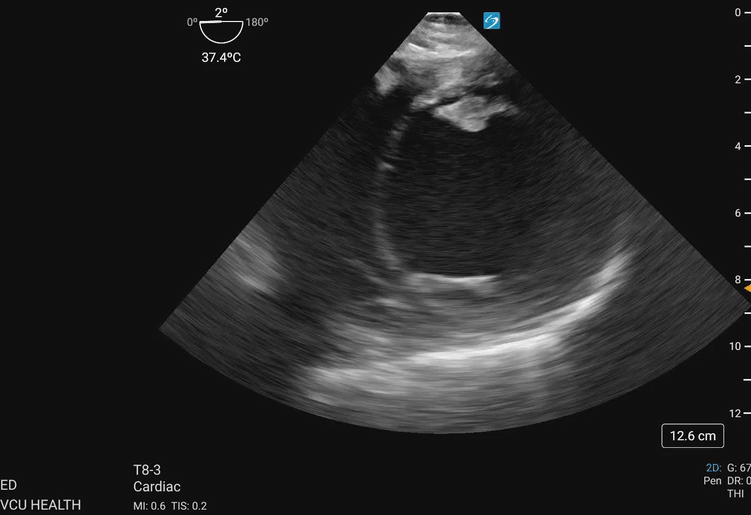

In the focused approach utilized in resuscitative TEE, evaluation of regional wall motion abnormalities in the major vascular territories of the left anterior descending (LAD), left circumflex (LCx), and right coronary artery (RCA) can be performed using the TG SAX view at the level of the midpapillary plane. To obtain this view, the operator will advance the TEE probe to an approximate depth of 40cm from the incisors, set the omniplane angle between 0-20 degrees, and anteflex the probe sufficiently to obtain the view demonstrated in Figure 1 and Figure 2. With slight adjustments in the depth of insertion further assessment of the base and apex of the left ventricle can be obtained.

Figure 2. Transgastric midpapillary view demonstrating the left ventricle and papillary muscles visualized at approximately 40cm depth from the incisions, omniplane between 0-20 degrees, and anteflexion of the probe. This patient demonstrates global left ventricular hypokinesis. Image courtesy of Lindsay Taylor, MD.

Figure 3a. Walls of the left ventricle as seen on TGSAX with vascular territories. The left ventricle here demonstrates global hypokinesis rather than pathology isolated to one vascular territory. Image courtesy of Lindsay Taylor, MD.